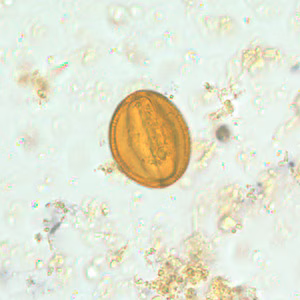

Pollen grains in stool.